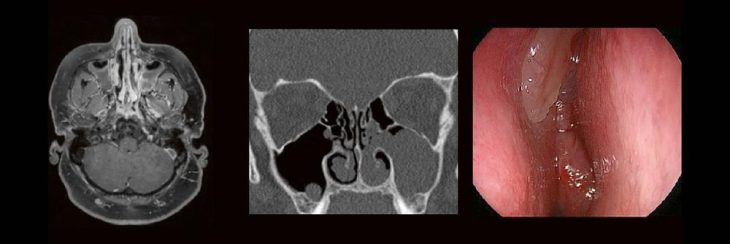

Professor Dr. med. Marc Brockmann WEITERENTWICKLUNGEN VON KOPF BIS FUSS BEIM VC Oberstarzt Dr. med. Stephan Waldeck DEEP-LEARNING-REKONSTRUKTION IN DER NEURORADIOLOGIE Die CT ist ein essentielles Routine-Verfahren in der Neuroradiologie. Bei steigender Bildqualität konnte die Röntgendosis mit neuen Technologien in der letzten Dekade deutlich gesenkt werden, was für die zielgerichtete und möglichst schonende Behandlung vonRead more about DEEP-Learning-Rekonstruktion in der Neuroradiologie (Webinar | Online)[…]